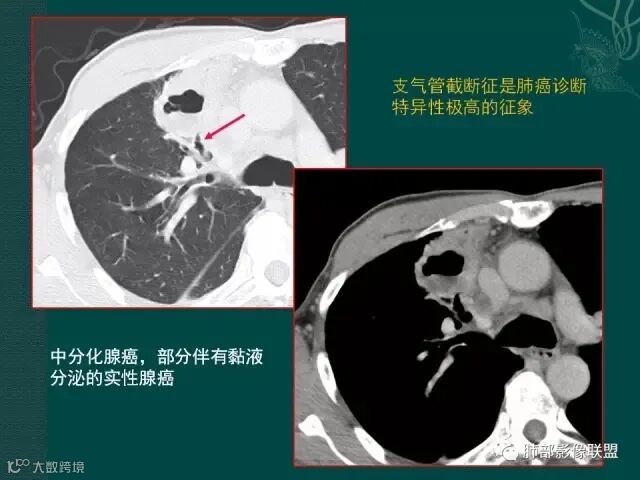

第一个是肺腺癌,边缘有毛刺,多发小空泡,直径不到5mm;

洞壁的血管,腺癌常见,鳞癌较少,结核罕见